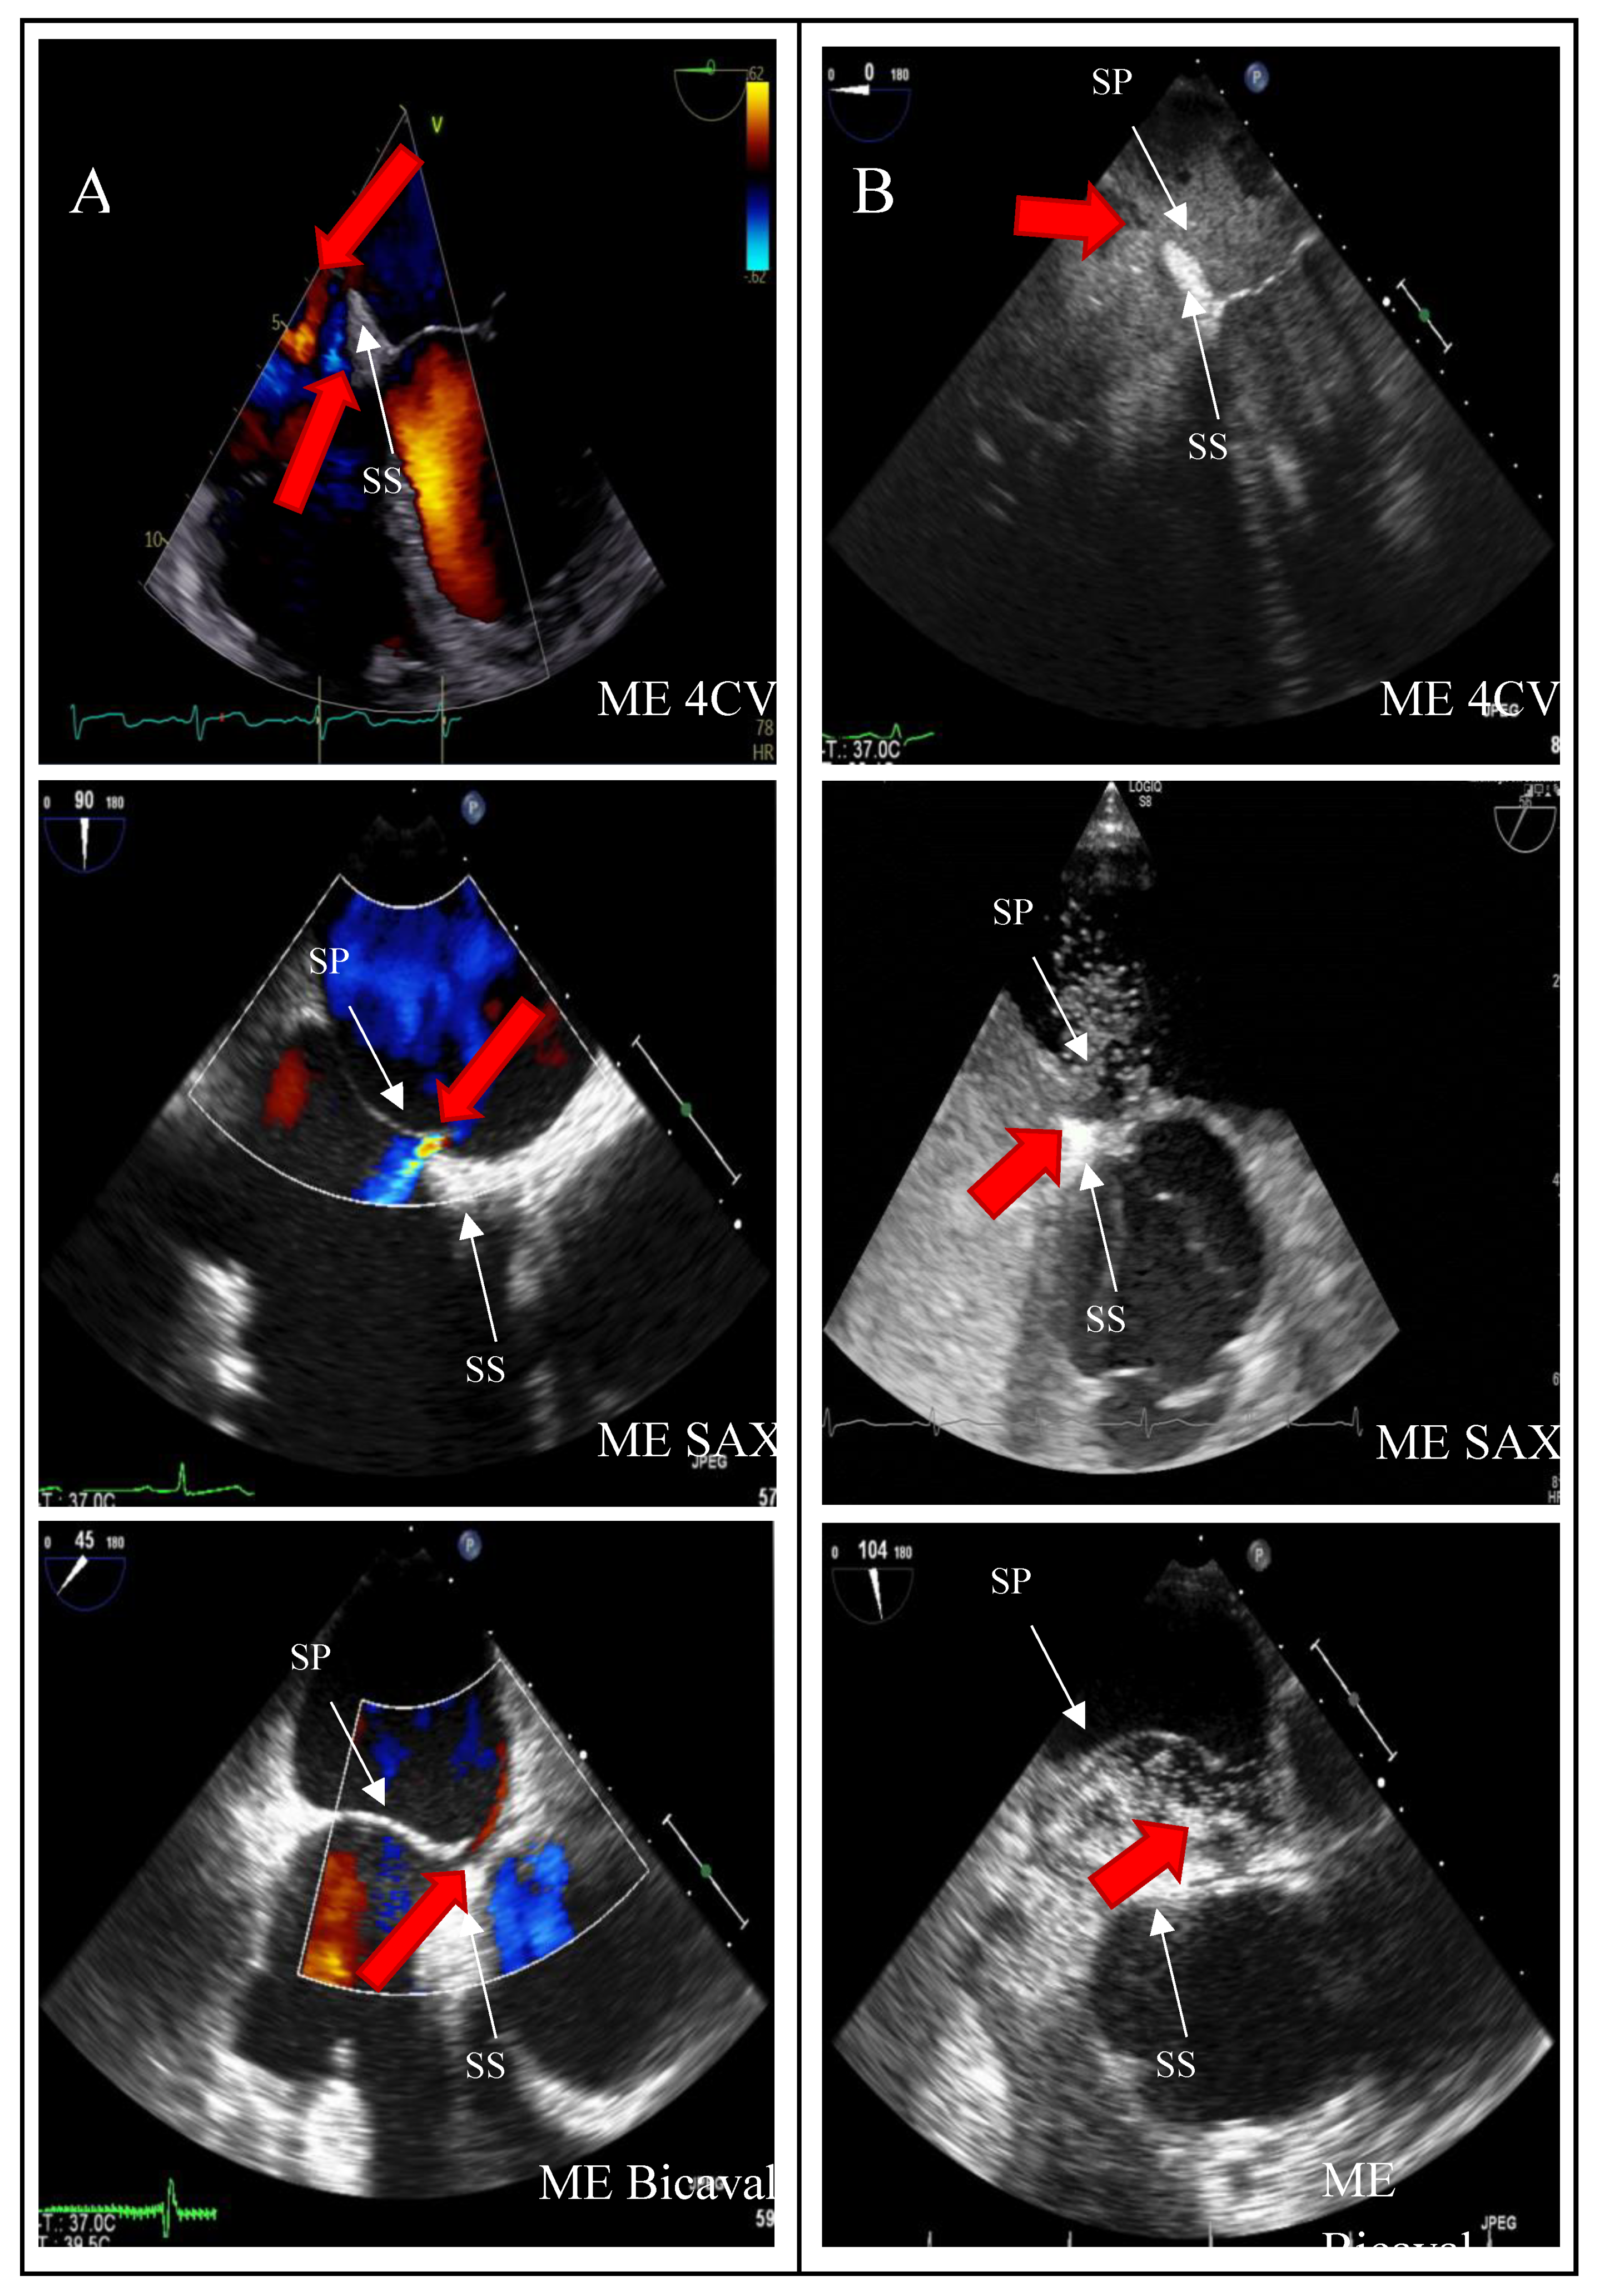

Background: Transesophageal echocardiography (TEE) is regarded as the gold standard for diagnosing patent foramen ovale (PFO). However, the occurrence of false positive PFO diagnoses is common in clinical practice, which may lead to unnecessary percutaneous interventions, as PFO occluders can only be placed when PFO presence is unequivocally confirmed. Various medical societies recommend a systematic protocol for the thorough assessment of the interatrial septum. Purpose: This study aimed to evaluate the incidence of false positive PFO diagnoses and analyze the underlying causes of misdiagnosis by comparing imaging data. Methods: In this retrospective observational study, we included 346 patients who were diagnosed with PFO following a cryptogenic ischemic stroke from January 2012 to December 2021. We first assessed the incidence of false positive PFO diagnoses. Subsequently, we compared stored imaging sequences from the screening TEE examinations with recommended diagnostic protocols outlined in European and American guidelines, identifying sources of diagnostic error. Results: The patient cohorts were divided into two groups: Group A consisted of 20 patients (5.8%) with PFO misdiagnoses, while Group B included 326 patients (94.2%) with accurate PFO occlusions. Our review of guideline compliance revealed that imaging planes in the mid-esophagus were used significantly more frequently than modified transgastric probe positions in the upper esophagus (71-96% vs. 1-2%). Three-dimensional imaging of the interatrial septum (IAS) was rarely utilized (0-3%), and the stepwise enlargement of the transducer angle in 15° increments was only partially documented. Comparisons between the two subgroups indicated reduced utilization of the bicaval viewing plane in the middle esophagus for the false positive group (Group A: 50% vs. Group B: 87%, p<0.001). The bubble test was performed in 80% of the misdiagnosis group using the short axis view, compared to 63% in the control group, while the bicaval view was utilized 30% of the time in the misdiagnosis group versus 47% in the control group (p=0.13 for both). IAS presentation in x-plane mode was consistently low across both groups (Group A: 20% vs. Group B: 17%, p=0.76). Conclusion: The incidence of false-positive PFO diagnoses before procedures was found to be 5.8% over the past decade. To mitigate such misdiagnoses, we identified three critical quality criteria that should be incorporated into all TEE examinations: 1) 2D imaging in the short axis view at the aortic valve level (30-75°), 2) 2D-imaging in the bicaval axis view (90-120°), and 3) a bubble test performed in conjunction with these views utilizing x-plane mode.

| SP | Septum primum |

| SS | Septum secundum |